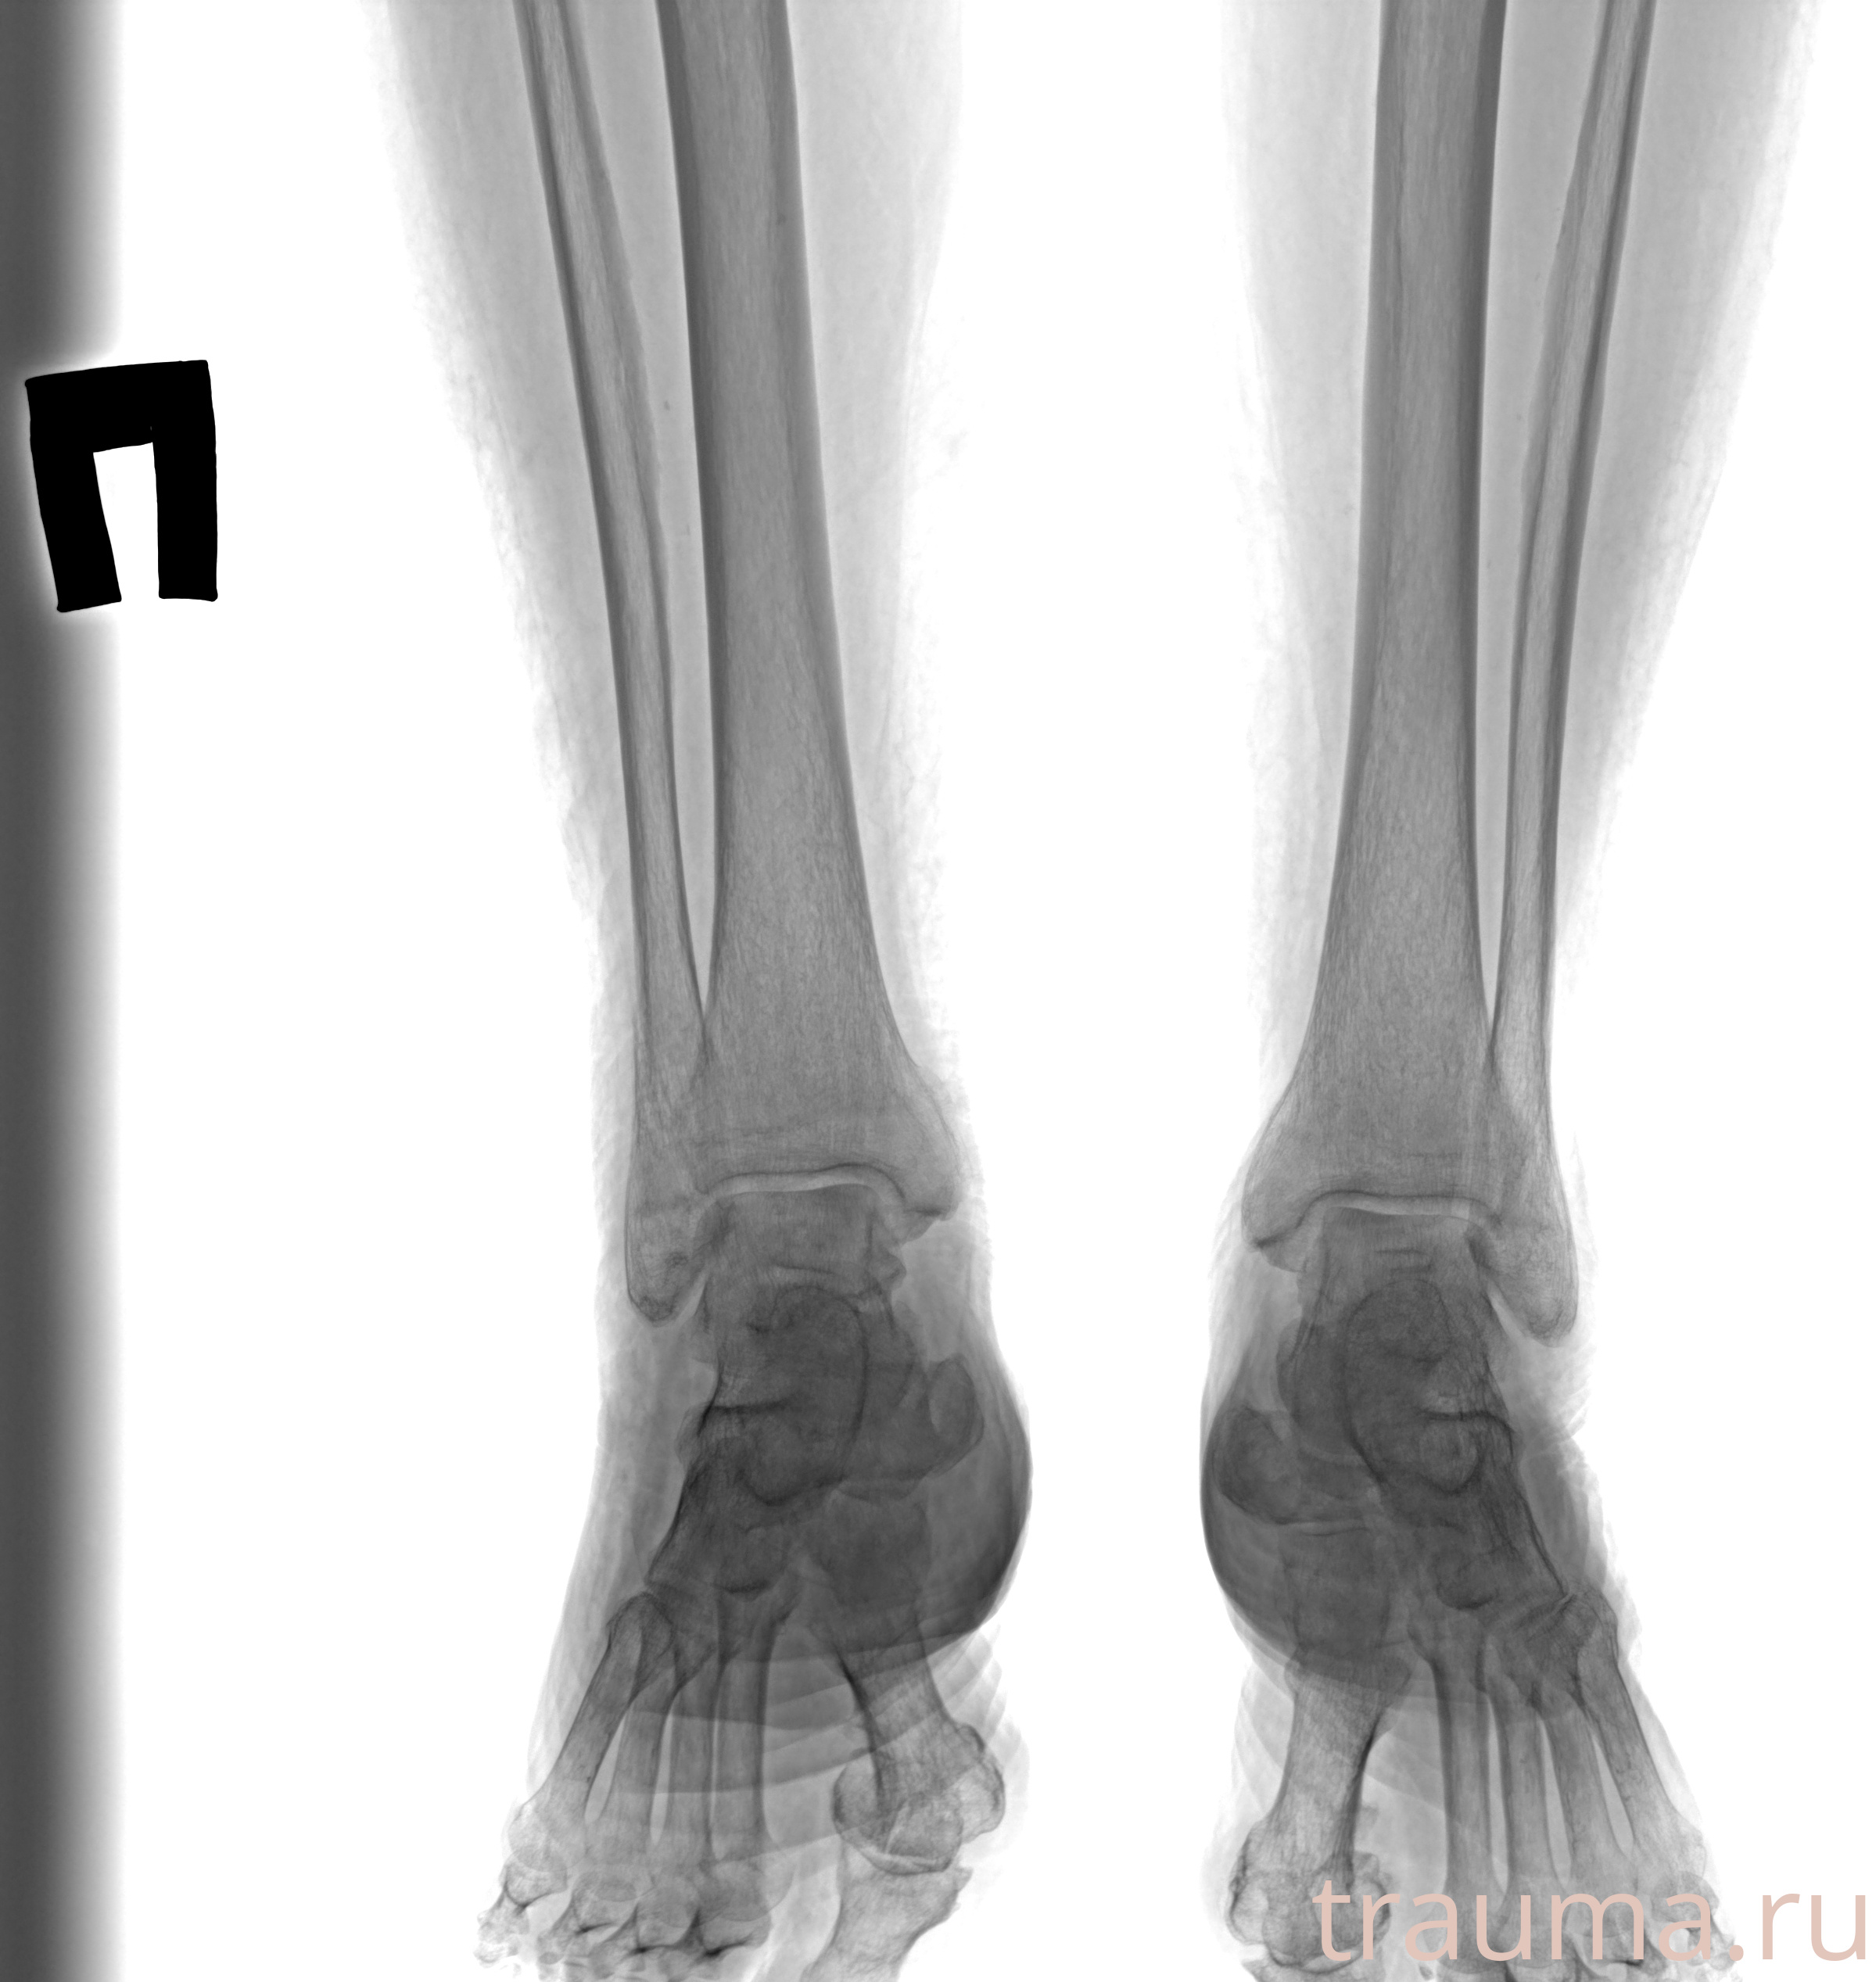

Рентгенограммы

Рентген на дому: по вашему адресу приезжает врач-рентгенолог, травматолог-ортопед с мобильным рентгеновским аппаратом, проводит диагностику травмы или заболевания, делает необходимые рентгенограммы, дает рекомендации по дальнейшему лечению. Получить качественные снимки в домашних условиях возможно благодаря уникальной методике, разработанной МосРентген Центром для института  Склифосовского